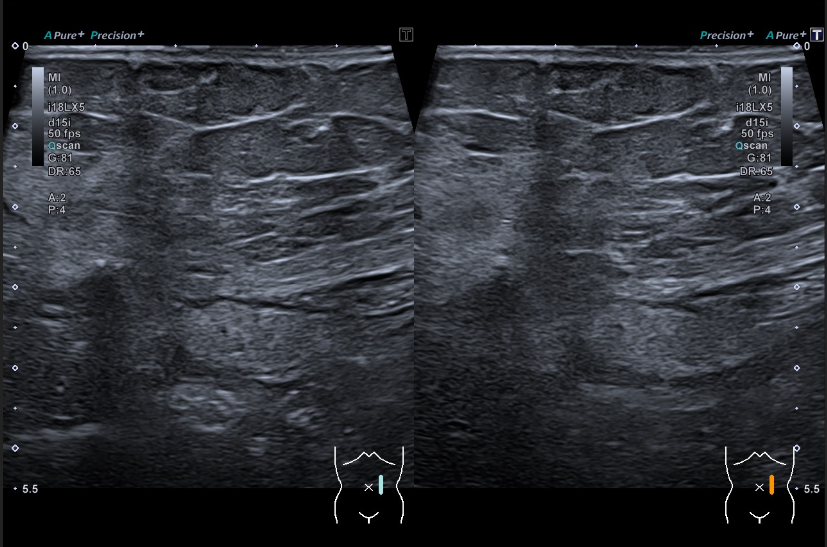

Se realiza una ecografía abdominal en el centro de salud visualizándose una masa hiperecogénica de 15 centímetros, aproximadamente, que parece dependiente del riñón derecho.

Se deriva a la paciente a urgencias hospitalarias donde se realiza una analítica sin objetivarse hallazgos significativos y una nueva ecografía en la que se visualiza una gran formación quística en flanco derecho que impresiona depender del riñón derecho. De manera ambulatoria se realizan un TC toraco-abomino-pélvico y una RMN abdomino-pélvica hallándose una masa abdomino-pélvica derecha de 15 x 13,5 x 12 centímetros de diámetros transversal, craneocaudal y anteroposterior, respectivamente, que impresiona de origen retroperitoneal vs origen ovárico.